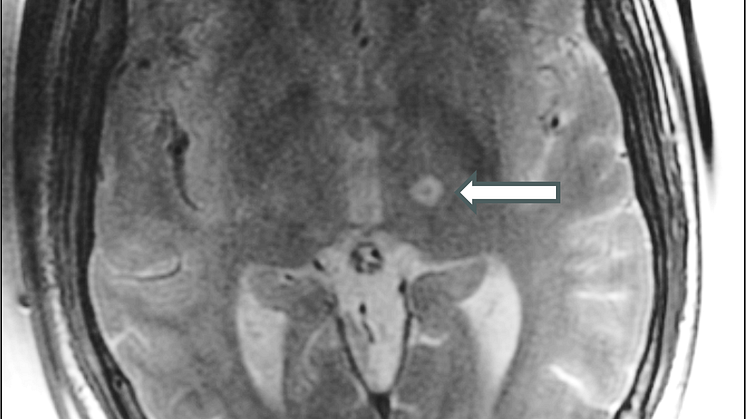

Metoden innebär att patienten placeras i en magnetkamera med en ultraljudshjälm. Området, punkten, som ger upphov till skakningarna identifieras med hjälp av bilder från magnetkameran och fler än 1 000 ultraljudskällor riktas mot denna punkt under drygt 10 sekunder. Där dessa sammanstrålar ökar värmen och ett 1–3 millimeter stort området inaktiveras. Men först testas effekten med lägre temperatur för att undvika eventuella biverkningar.